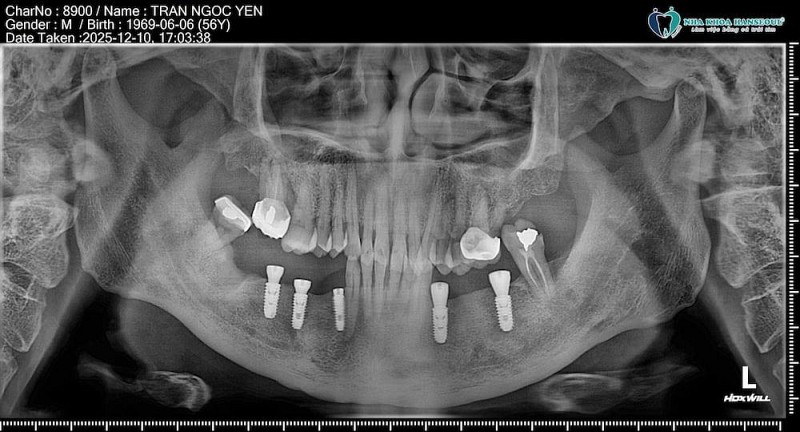

Đoàn bác sĩ và điều dưỡng giàu kinh nghiệm của Hanseoul đã trực tiếp đến trụ sở Wichita, tiến hành kiểm tra răng miệng cho toàn bộ nhân viên theo quy trình tiêu chuẩn. Các bước khám bao gồm: đánh giá khoang miệng, kiểm tra tình trạng nướu, phát hiện sâu răng, viêm lợi, mòn răng, sai lệch khớp cắn và sàng lọc các dấu hiệu bất thường khác.

Chỉ trong một buổi khám, đội ngũ chuyên môn của Hanseoul đã ghi nhận nhiều vấn đề răng miệng phổ biến ở dân văn phòng, đặc biệt là những người làm việc liên tục với máy tính và thường xuyên ăn uống vặt trong giờ làm.

Qua thăm khám, các bác sĩ chỉ ra một số tình trạng xuất hiện với tần suất cao:

- Sâu răng sớm do thói quen ăn đồ ngọt, uống trà – cà phê nhiều lần trong ngày.

- Viêm lợi và chảy máu chân răng do vệ sinh răng chưa đúng cách.

- Ê buốt răng liên quan đến tụt lợi, mòn cổ răng.

- Răng khấp khểnh nhẹ gây khó vệ sinh, dễ tích tụ mảng bám.

- Nghiến răng, đau khớp thái dương hàm do áp lực công việc kéo dài.

Đây đều là những vấn đề âm thầm tiến triển, dễ bị bỏ qua khi chưa có triệu chứng rõ ràng, vì vậy việc khám định kỳ giúp phát hiện sớm và điều trị kịp thời.